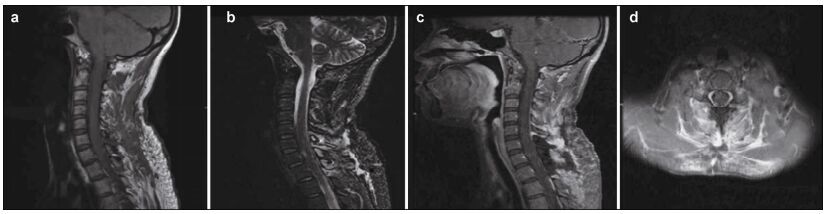

2 Case reportA 35-year-old woman presented to Beijing Tsinghua Changgung Hospital with a 10-year history of cervical malaise, which rapidly worsened over the 3 months prior to presentation. Her symptoms included right limb paraesthesia and gait deterioration due to imbalance and weakness. Her past medical and family histories did not support a neurofibromatosis diagnosis.A neurologic examination revealed grade 4 right limb muscle strength, as well as right limb pain and numbness. A right Hoffman sign (+) and exaggerated right tendon reflexes were also observed. MRI revealed an 8 mm × 6 mm × 8 mm intramedullary tumor at the C6-C7 vertebrae level. The tumor had clear margins, was isointense on T1-weighted images (Figure 1a), and was slightly hyperintense on T2-weighted images (Figure 1b). Marked homogenous contrast enhancement was also noted (Figures 1c-1e) and there were some signs of swelling around the lesion. After intraoperative O-arm navigation to determine the lesion's exact location, a small explosive incision was made in the spinal cord, between the C6 and C7 vertebrae. The tumor had clear margins and was highly adherent to the surrounding neural tissues. The tumor was completely resected using microsurgical techniques. It was a solid, soft mass, measuring approximately 8 mm × 5 mm × 2 mm. A pathological examination confirmed that the tumor was a schwannoma (Figure 1f). The patient's neurological examination improved postoperatively. One year after surgery, the patient's symptoms were in remission and a post-operative MRI revealed no evidence of tumor recurrence (Figures 2a-2d).

| Figure 1 (a) Sagittal T1-weighted magnetic resonance image demonstrating an isointense lesion. (b) Sagittal T2-weighted magnetic resonance image demonstrating a slightly hyperintense lesion, with swelling surrounding it. (c-e) Sagittal, coronal, and axial T1-weighted magnetic resonance images, with gadolinium contrast, demonstrating homogeneous enhancement of the tumor. The tumor appears as a solid mass, located to the right side of spinal cord, with clear margins. (f) Hematoxylin and eosin staining from the biopsy of the mass showing bipolar spindle cells with nuclei arranged in a palisade pattern (Hematoxylin & Eosin stain; magnification, ×100) |

The specific clinical manifestations of intramedullary schwannomas are associated with the tumor's size and location, but they generally exhibit the general characteristics of intramedullary tumors in that they cause upper motor neuron damage. Patients often complain of numbness, pain, paralysis, muscle atrophy, and even dyspnea. Wu et al. reported that somatic and nerve root pain are the chief complaints associated with schwannomas[14]. MRI is the most useful modality for diagnosing spinal cord tumors, but little research on intramedullary schwannomas has been reported.Our literature review indicated that schwannoma characteristics include: (1) asymmetric, solid nodules or masses, often located in the dorsolateral part of the spinal cord; (2) most lesions are small, spanning no more than three vertebral segments; (3) T1-weighted MRIs generally show an isointense or slightly hypointense lesion, T2-weighted scans show slightly hyperintense lesions, and enhanced T1-weighted scans show homogeneous enhancement, with obviously clear margins; (4) the lesions may be accompanied by cystic changes, necrosis, syringomyelia, localized swelling, and rarely, calcification[3, 6-12, 15].

Based on the articles reviewed, the most common differential diagnoses associated with intramedullary schwannomas include ependymomas, hemangioblastomas, astrocytomas, and intramedullary tuberculomas[1-7, 10-12, 14, 15]. The preoperative diagnosis of the present case was hemangioblastoma. However, the enhancement of the lesion was less obvious than that typical of a hemangioblastoma, and extensive cystic changes and vascular flow-void effects were not observed. There was also evidence of swelling, which differentiated the present lesion from a hemangioblastoma.